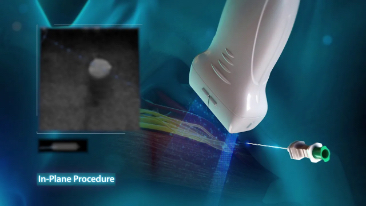

Since the company was founded, Mindray has been continuously exploring new ways to improve diagnostic confidence. Powered by the most revolutionary ZONE Sonography? Technology, Resona 7ŌĆÖs new ZST+ platform brings ultrasound image quality to a higher level by zone acquisition and channel data processing.

As well as the premium level image quality, Resona 7 also enhances clinical research capabilities with the revolutionary V Flow for vascular hemodynamic evaluation, and the most intelligent plane acquisition from 3D datasets for fetal CNS diagnosis. Combining the most intuitive gesture-based multi-touch operation and all the essential clinical features, Resona 7 is truly leading new waves in ultrasound innovation.